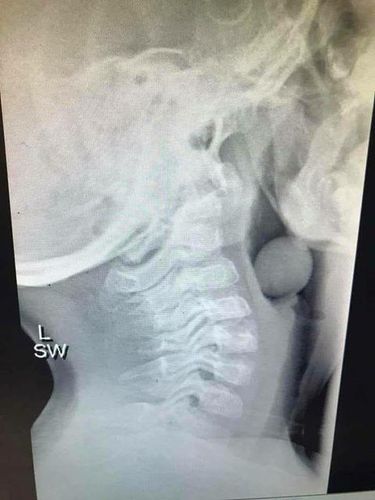

Petugas kesehatan mental sekaligus blogger Angela Henderson mengupload foto x-ray di halaman Facebook-nya 'Finlee and Me' setelah mendapat persetujuan dari orang tua sang anak. Dalam tulisannya Angela mengatakan sang anak perlu dioperasi untuk mengeluarkan buah anggur.

"Dia sangat beruntung karena sebagian saluran udaranya masih terbuka karena kalau tidak ini akan berakhir dengan sangat buruk," lanjut Angela.

Foto: Facebook / Finlee and Me |

Foto: Facebook / Finlee and Me